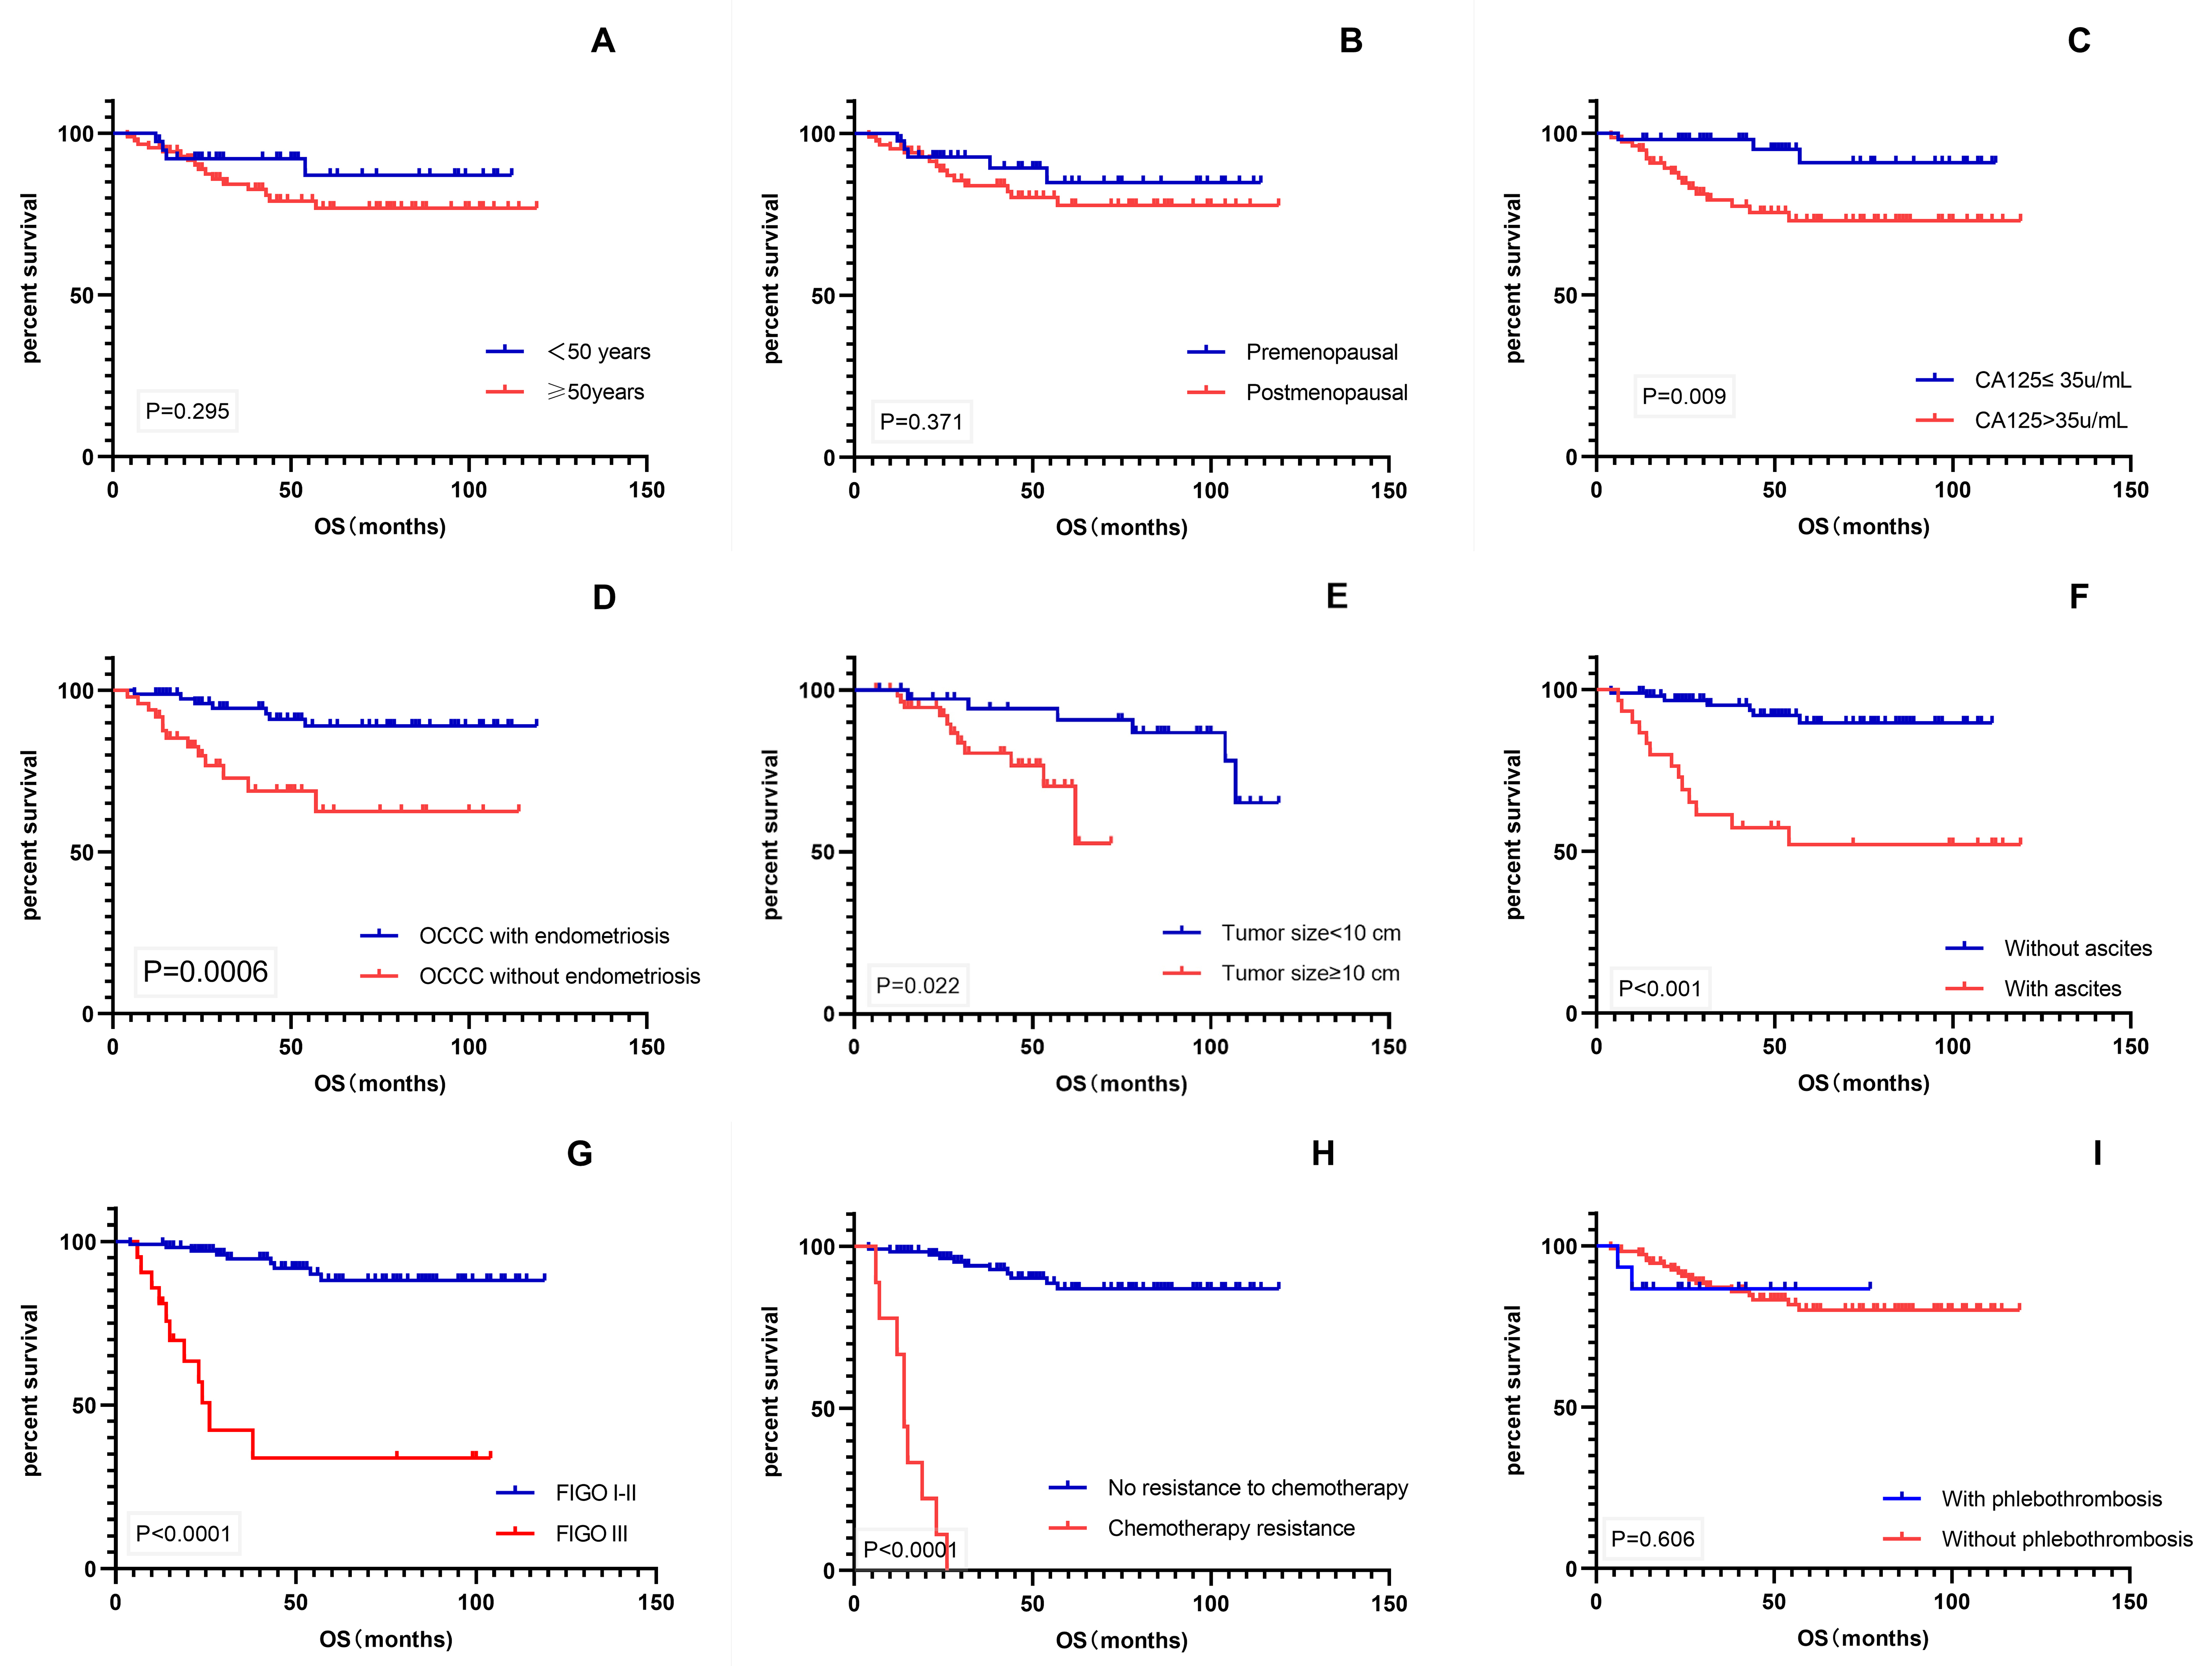

Kaplan–Meier univariate analysis using survival time as the dependent variable

was performed for various factors that might affect patient prognosis (Fig. 3).

The results showed that CA-125 level, endometriosis, tumor size, ascites, FIGO

stage, and chemotherapy resistance were significant prognostic factors for OS

(p

Fig. 3.

Fig. 3.Kaplan–Meier survival curves. (A–I) OS of patients with age, menopausal status, CA-125 level, endometriosis, tumor size, ascites, FIGO stage, chemotherapy resistance, and phlebothrombosis. OS, overall survival; CA-125, cancer antigen 125; FIGO, International Federation of Gynecology and Obstetrics.